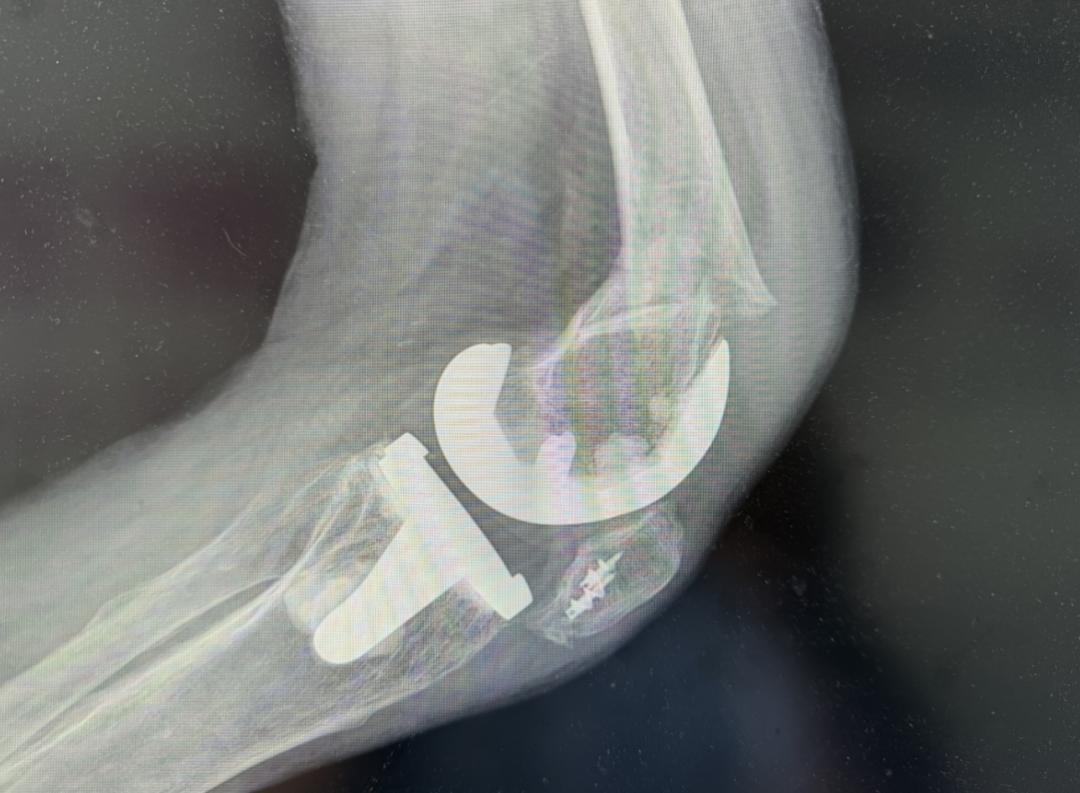

经骨科医生详细检查,诊断王大爷为“左股骨远端骨折”,同时发现骨折的位置非常特殊——就发生在去年置换的人工膝关节假体周围,属于临床上处理难度较大的“假体周围骨折”。此外,影像学检查也提示存在“左膝关节人工关节置换术后改变”及“左膝关节退行性变”。为了获得专业救治,王大爷被迅速以“左膝假体周围骨折”收入骨科病房。

针对这一复杂的假体周围骨折病例,我院骨科团队进行了多学科会诊,制定了周密的"左膝假体周围骨折切开复位内固定术"方案。手术中,医生们精细操作,在保护原有膝关节假体和周围组织的前提下,精准复位骨折块并选用特殊锁定钢板固定。整个手术过程在影像设备实时监控下完成,这种精准的手术方式不仅成功修复了骨折,更保护了患者原有的关节功能,为术后康复奠定了坚实基础。